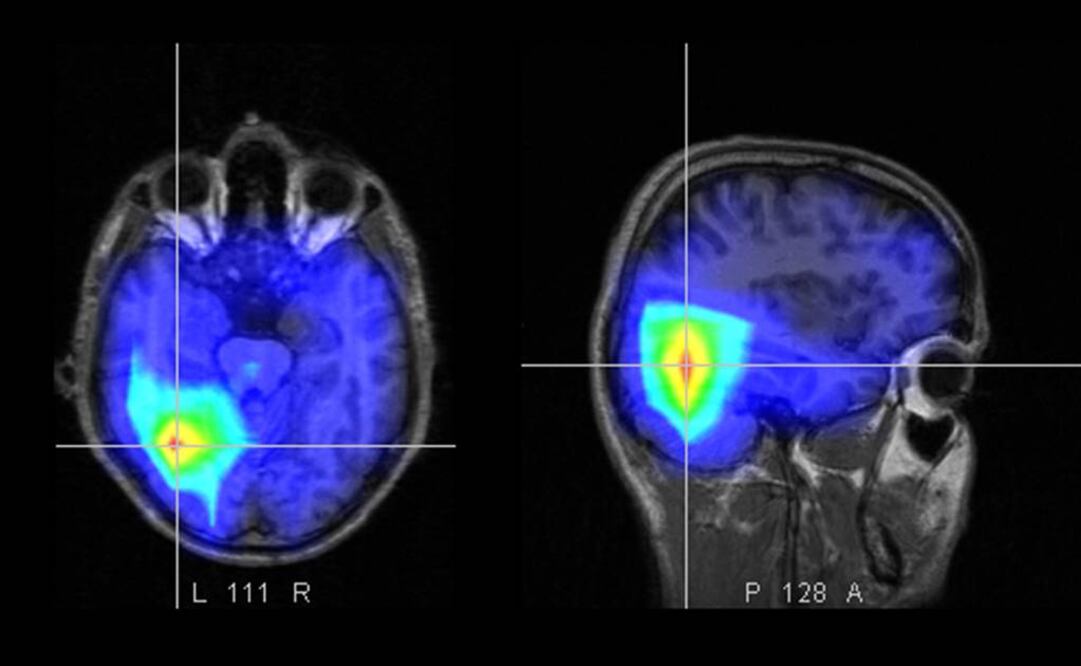

En una explicación más detallada se define a la optogenética como una técnica que se basa en el uso de proteínas microbianas que pueden ser activadas por la la emisión de luces de alta precisión, es así que en el laboratorio de Ofer Yizhar se insertan estas proteínas sensibles a la luz en una selección de neuronas para probar diversas hipótesis con respecto a la disfunción de circuitos neuronales asociados a ciertas enfermedades.

Yizhar señala que el reto inmediato de los científicos es detectar cuáles circuitos de neuronas son las que se tienen que manipular para aliviar los síntomas de una enfermedad.

El investigador explica que en el caso del Parkinson cuando la enfermedad esta muy avanzada ya no hay respuesta a los tratamientos farmacológicos y se vuelven candidatos a una Estimulación Cerebral Profunda (DBS), un tratamiento neuroquirúrgico estándar para tratar de disminuir los daños motores de la enfermedad como rigidez, temblores y episodios de desvanecimiento y discinesias.

Creo que teóricamente si supiéramos en cuáles poblaciones de neuronas radica el efecto terapéutico y cuáles debemos evitar porque su manipulación puede tener un efecto contraproducente, entonces podríamos realizar las aplicaciones de optogenética de manera más dirigida, que simplemente un estimulo eléctrico no selectivo”.